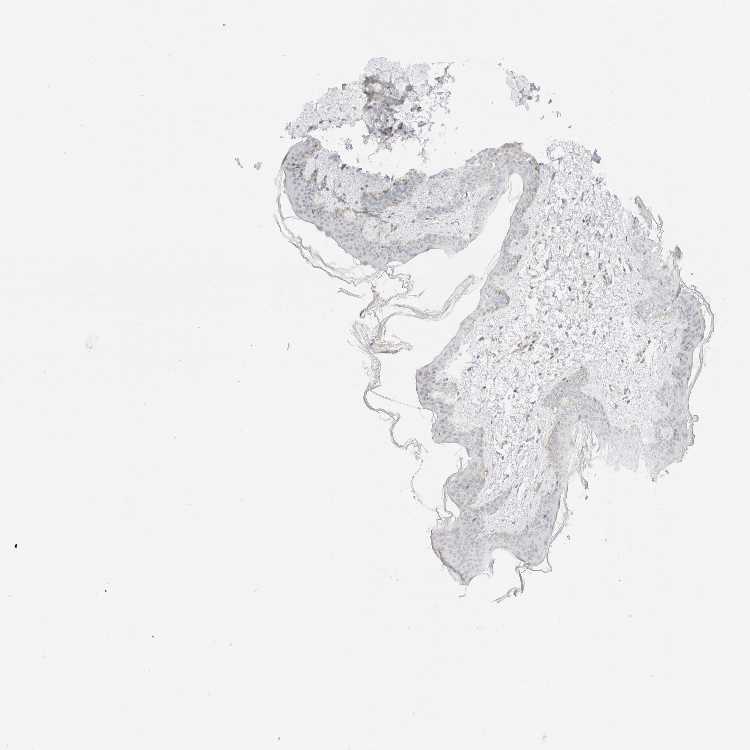

SKIN 1 - Antibody stainingi

Antibody staining in the annotated cell types in the current human tissue is reported as not detected, low, medium, or high, based on conventional immunohistochemistry profiling in selected tissues. This score is based on the combination of the staining intensity and fraction of stained cells.

Each image is clickable and will lead to virtual microscopy that enables deeper exploration of all samples and also displays staining intensity scores, fraction scores and subcellular localization as well as patient and tissue information for each sample.

Antibody HPA024702Antibody CAB017041

Langerhans MediumMedium

Fibroblasts MediumLow

Keratinocytes Not detectedLow

Melanocytes MediumMedium

SKIN 2 - Antibody stainingi

Epidermal cells LowMedium